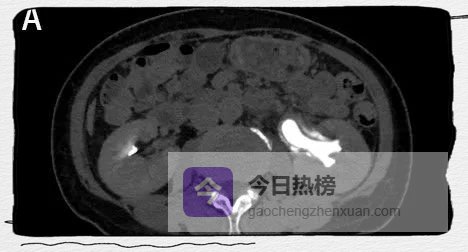

图3B

图3A、B

CT增强排泄期则显示内腔密度增高。